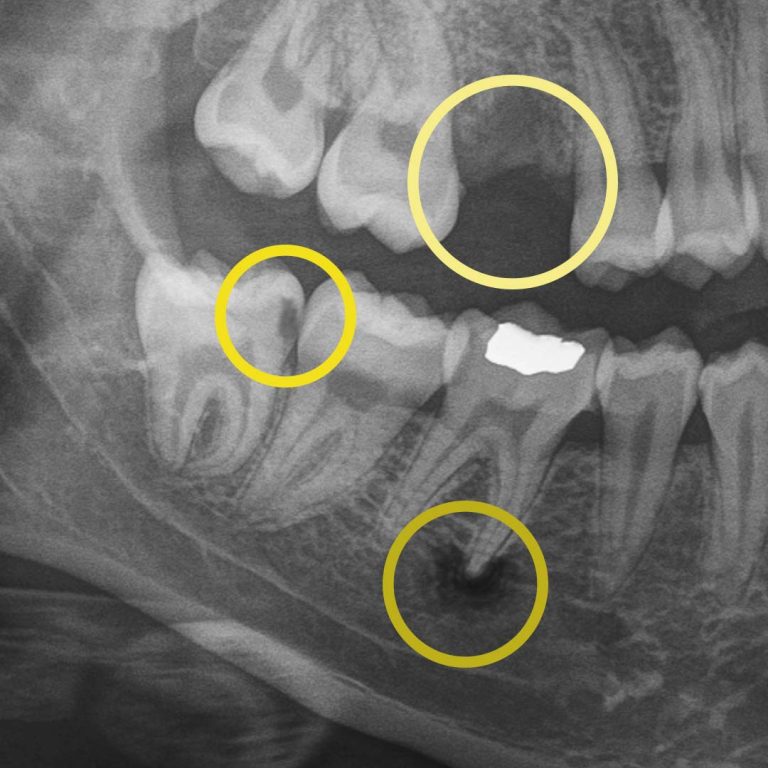

For example, during a routine digital X-ray, we may notice a small shadow between two teeth. To the naked eye, everything can look healthy, but that faint shadow often tells us the enamel in that area is starting to weaken. This is considered early-stage tooth decay, sometimes called early “caries.”

Before this decay turns into a hole in the tooth, also known as a “cavity,” we can begin proactive treatment that can prevent the decay from worsening. A prescribed treatment like Curodont™ can repair the tooth (without drilling!) by helping guide minerals back into the enamel and supporting the tooth’s natural ability to heal when it’s paired with good brushing, flossing, and regular professional care. This approach allows us to be non-invasive and protect your natural tooth.

At your next X-ray visit, we’ll compare images to see whether that spot has stabilized or improved. If the area worsens and the enamel breaks down further, a small dental filling may be necessary to prevent deeper decay damaging the tooth structure. If the decay continues unchecked and reaches the inner portion of the tooth where the nerve lives, treatment becomes more complex, often requiring root canal therapy, which can be time-consuming, uncomfortable, and costly.